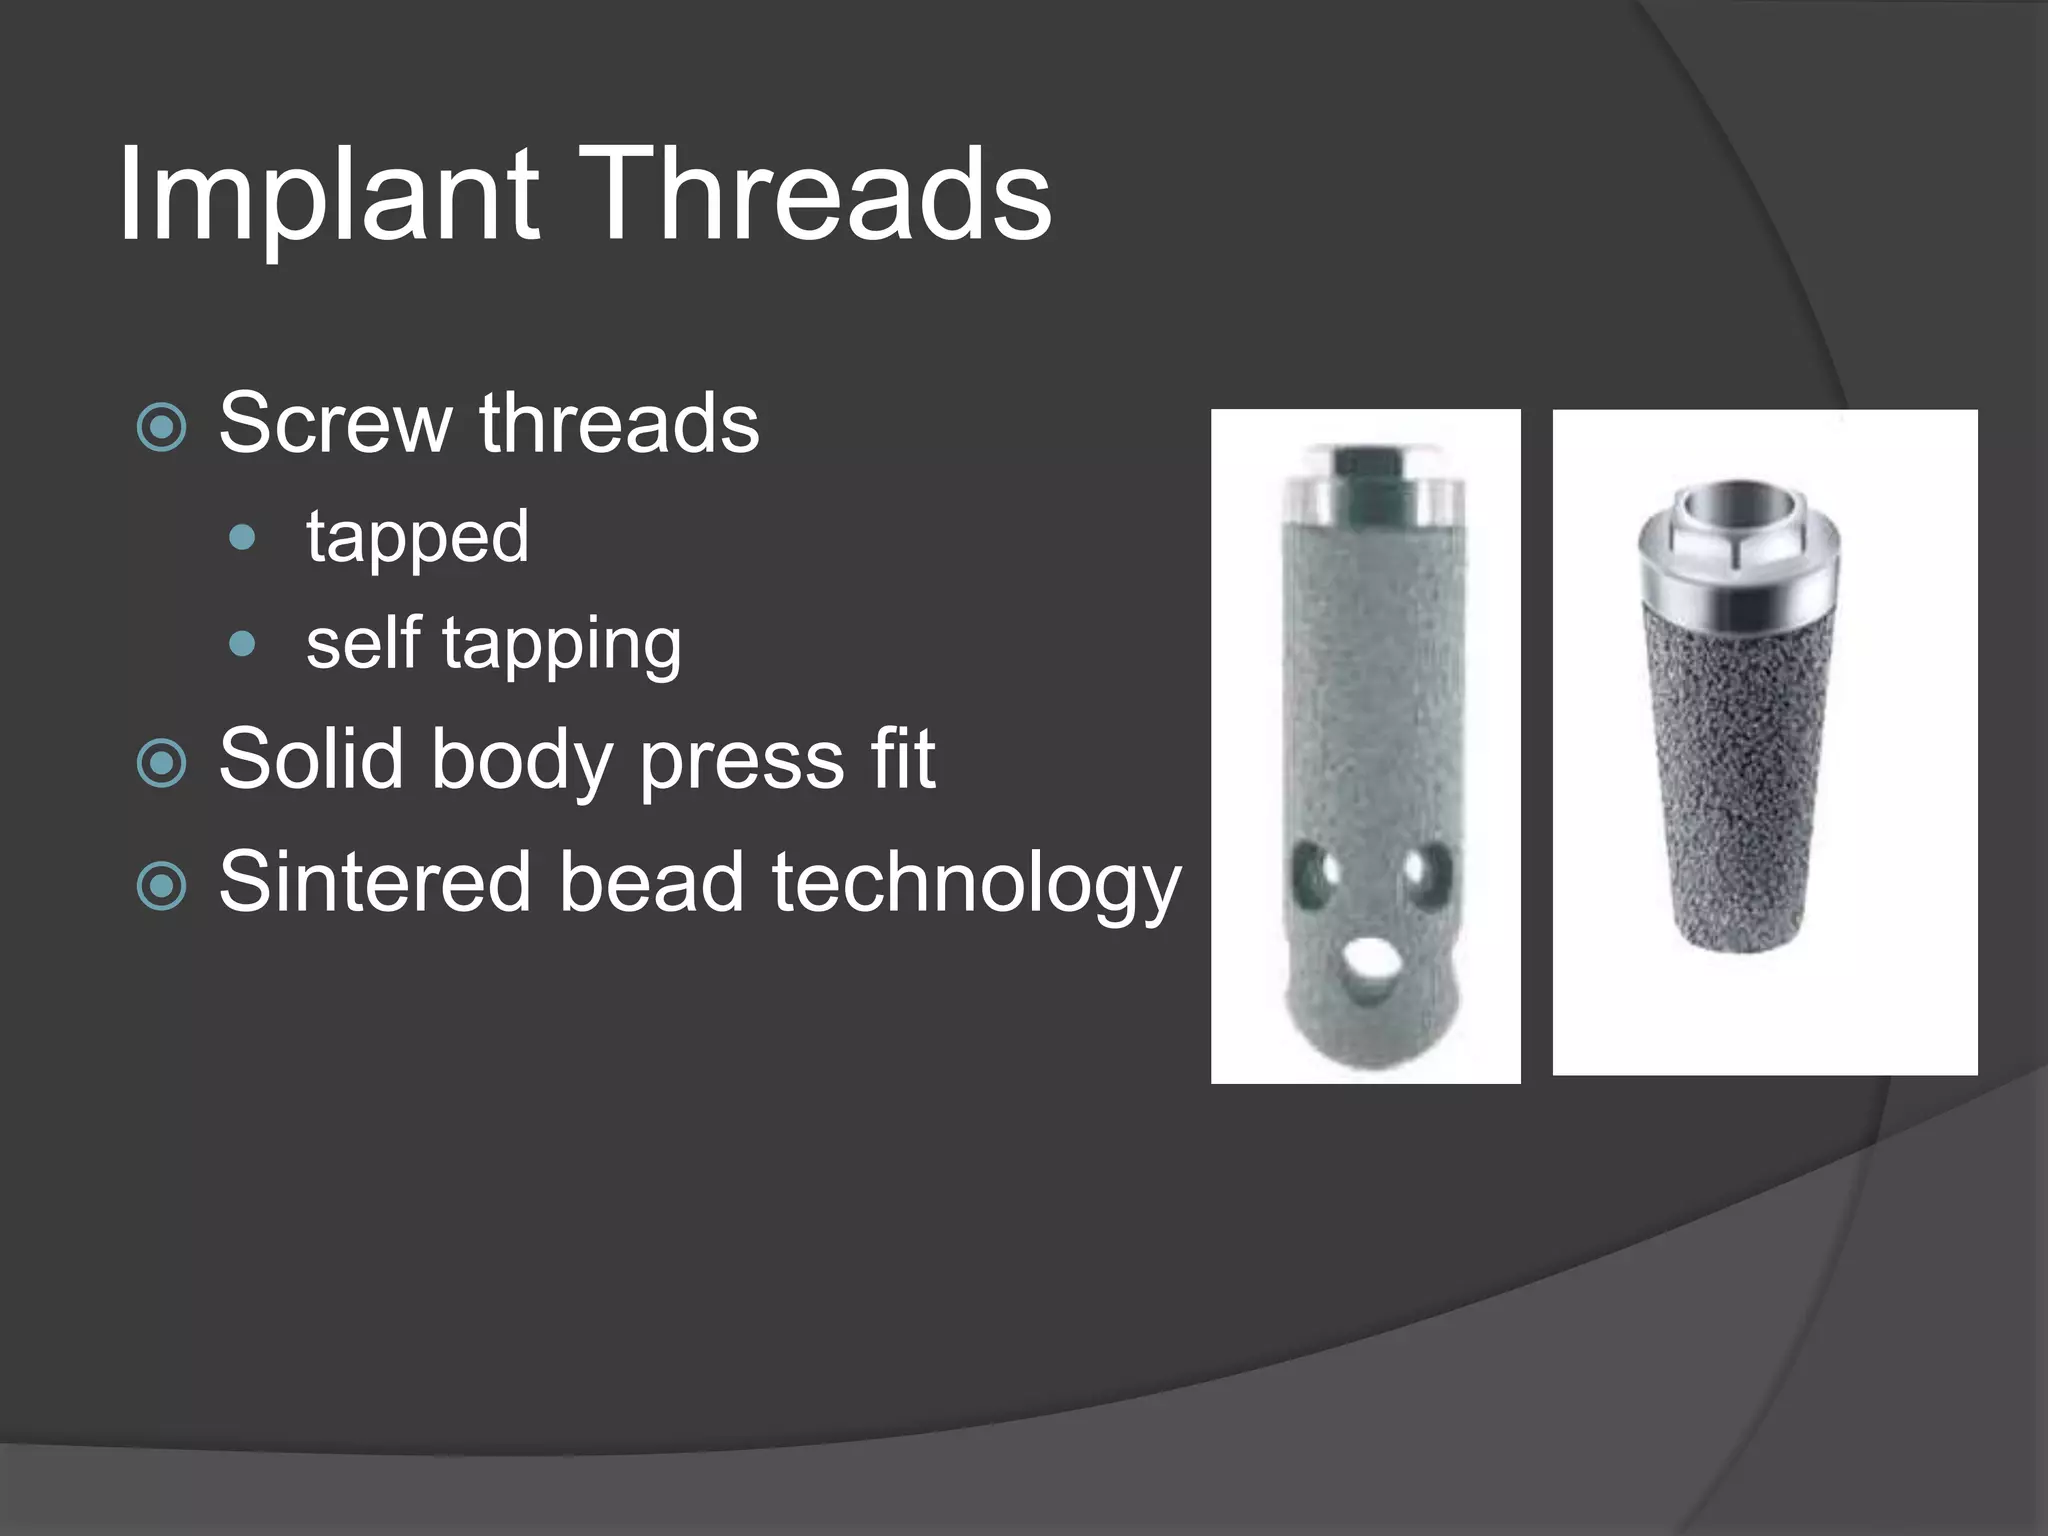

This document discusses factors that influence osseointegration and primary stability of dental implants, including implant design characteristics, surgical technique, and loading protocols. Specifically, it covers the processes of osseointegration and how forces on implants can either promote or inhibit bone remodeling. Key implant design considerations like length, diameter, threads, coatings and surface topography are analyzed in terms of their effects on stress distribution and bone-implant contact. The importance of primary stability and factors influencing it like bone quality and surgical skill are also addressed. Loading protocols ranging from immediate to conventional loading are compared.